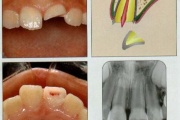

Krooni murrud